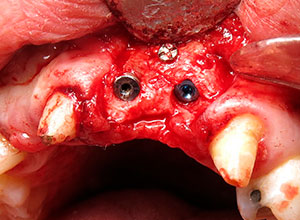

Con el Injerto óseo modelado, se procede a colocar en el defecto óseo, fijándolo con tornillos, para asegurar su estabilidad.

Se espera de 6 a 8 meses para lograr la integración del injerto, se descubre el área para la colocación de implantes dentales.